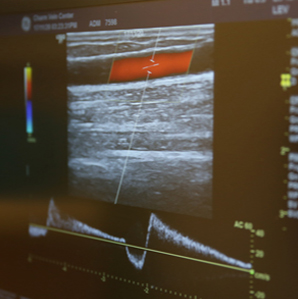

혈관초음파검사를 통하여

수술 여부를 확인합니다.